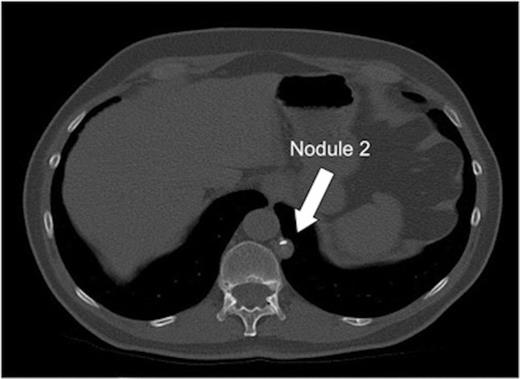

A 71 year old male Caucasian teacher was incidentally found on Computed Tomography (CT) of the colon to have two well-defined nodules in the left hemithorax. There was no other abnormality within the thorax or abdomen. He was a non-smoker, with only minimal exposure to a classroom with an asbestos roof. He had no history of chest trauma, intervention or pleurisy. A further high resolution CT scan of the chest demonstrated a well-defined rounded 11mm nodule arising from the pleura of the left diaphragmatic surface (Figures 1a and b). A larger 15mm rounded soft tissue lesion containing calcification was noted in the pleura of the left paravertebral region adjacent to the lower lobe (Figure 2). No other abnormality was present in the chest. The multidisciplinary decision at that time was to monitor with an interval high resolution CT scan of the thorax. Four months later the scan showed a slight increase in size of both nodules and a decision with the patient and by a multidisciplinary meeting was to resect the nodules for diagnosis. At this stage the nodules were in the same position as on the initial scan.

Transverse CT image of the thorax demonstrating nodule 2 adjacent to the mediastinum, vertebral body and descending aorta